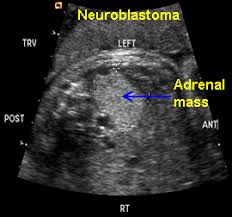

Kidney Ultrasound Adrenal Glands. It s hard to see normal adult adrenals on ultrasound despite being near the kidneys review of the adrenals in an adult is not part of the routine kidney ultrasound. An outer cortex and an inner medulla.

Ct scans also show the organs near the adrenal glands as well as lymph nodes and distant organs. 190 layers of adrenal gland. It s hard to see normal adult adrenals on ultrasound despite being near the kidneys review of the adrenals in an adult is not part of the routine kidney ultrasound.

Details of the adrenal glands. High resolution real time sonography allows visualization of normal adrenal glands in 71 92 of adults. The normal ascent of the kidneys allows the organs to take their place in the abdomen below the adrenal glands. The left adrenal gland is imaged by a posterolateral approach in coronal plane through the long axis of the left kidney.